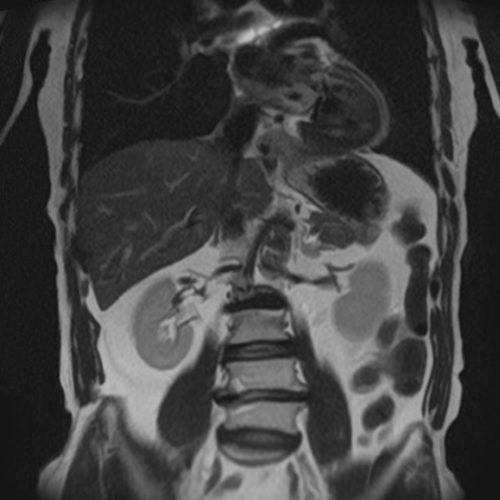

MRI検査とは

頭部検査においては、特に有用で、CT検査では発見できない急性期の脳梗塞を捉えることができ、早期診断・早期治療を可能にします。この他にも、脊椎・骨軟部・関節・腹部・骨盤腔(子宮・卵巣・前立腺)の病変に優れた描出能があり、様々な疾患の早期発見・診断に有用とされ、研究が進んでいます。

全身DWI

腹部